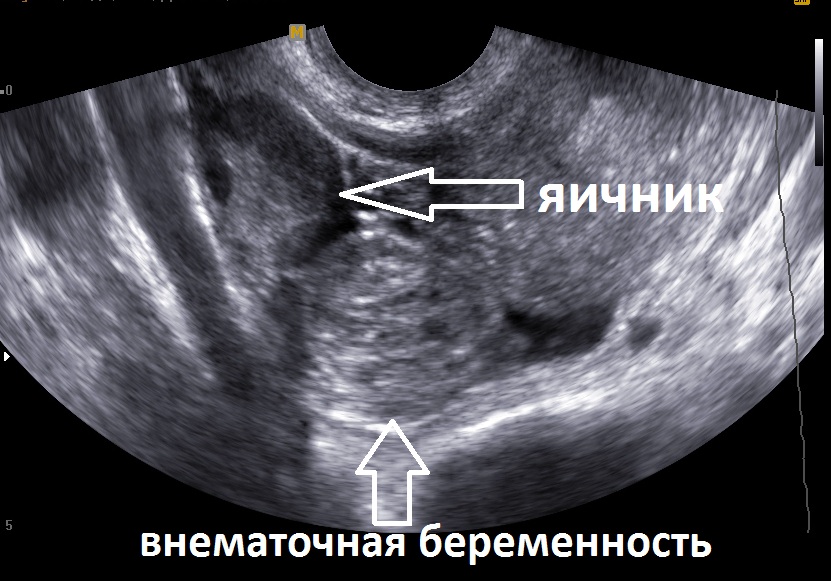

Для диагностики состояния чаще всего применяются следующие методы:

- УЗИ;

С помощью интравагинального УЗИ можно поставить диагноз уже на второй неделе. Но происходит такое редко. Так как женщины, обычно, обращаются к врачам куда позже.

Диагностика внематочной беременности обычно включает в себя гинекологический осмотр, анализы крови на уровень ХГЧ (хорионического гонадотропина человека) и ультразвуковое исследование. УЗИ помогает определить местоположение беременности и исключить нормальную маточную беременность.